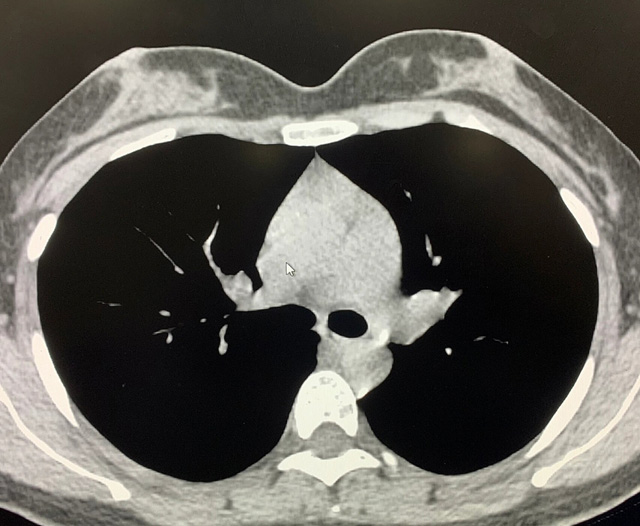

能譜純化技術(shù)的核心是通過物理濾過(如錫濾片)或軟件算法,選擇性濾除低能X射線光子,保留高能光子。在胸部低劑量CT掃描中顯著提升了圖像質(zhì)量與輻射劑量的平衡。

優(yōu)勢(shì)輻射劑量顯著降低相較于常規(guī)CT,輻射劑量減少約70%-90%,尤其適合需多次隨訪的高危人群(如肺癌篩查),降低輻射相關(guān)癌癥風(fēng)險(xiǎn)早期肺癌篩查效果明確可清晰檢測(cè)毫米級(jí)肺結(jié)節(jié),顯著提高早期肺癌檢出率,降低死亡率。檢查快捷且普及性高單次掃描僅需數(shù)秒,無需對(duì)比劑,設(shè)備廣泛配置于基層醫(yī)院,便于大規(guī)模篩查。長(zhǎng)期成本效益顯著雖單次費(fèi)用與常規(guī)CT相近,但早期干預(yù)可大幅降低晚期治療費(fèi)用及社會(huì)醫(yī)療負(fù)擔(dān)。技術(shù)優(yōu)化提升圖像質(zhì)量迭代重建算法(如ASIR、MBIR)在降低劑量同時(shí)減少噪聲,平衡影像質(zhì)量與安全性。